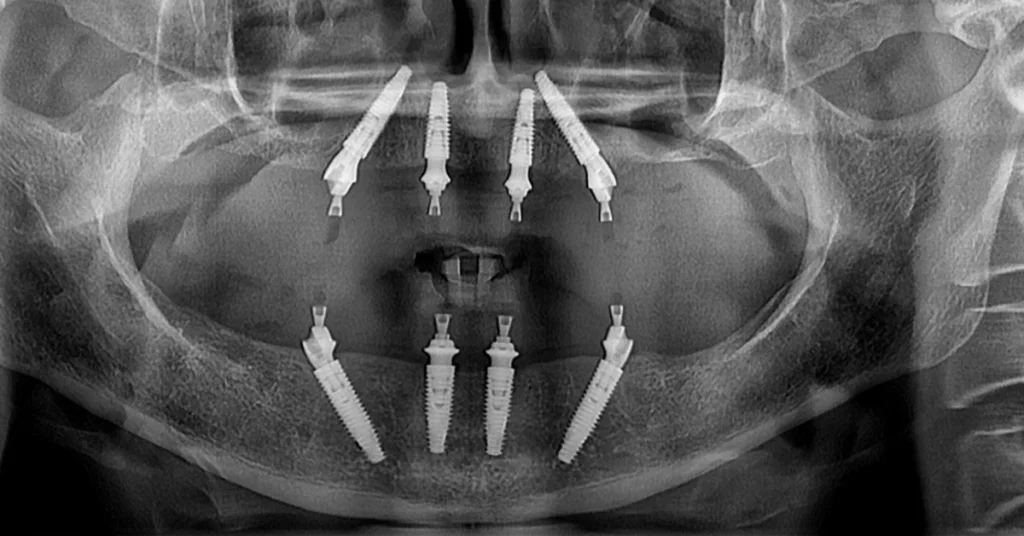

Tratament realizat pe 4 implanturi la maxilar, si 4 implanturi standard la mandibula. Pacienta a purtat o lucrare provizorie timp de 6 luni, iar la finalul acestor luni putem observa lucrarile finale din Ceramica Stratificata pe Zirconiu atat la maxilar cat si la mandibula.